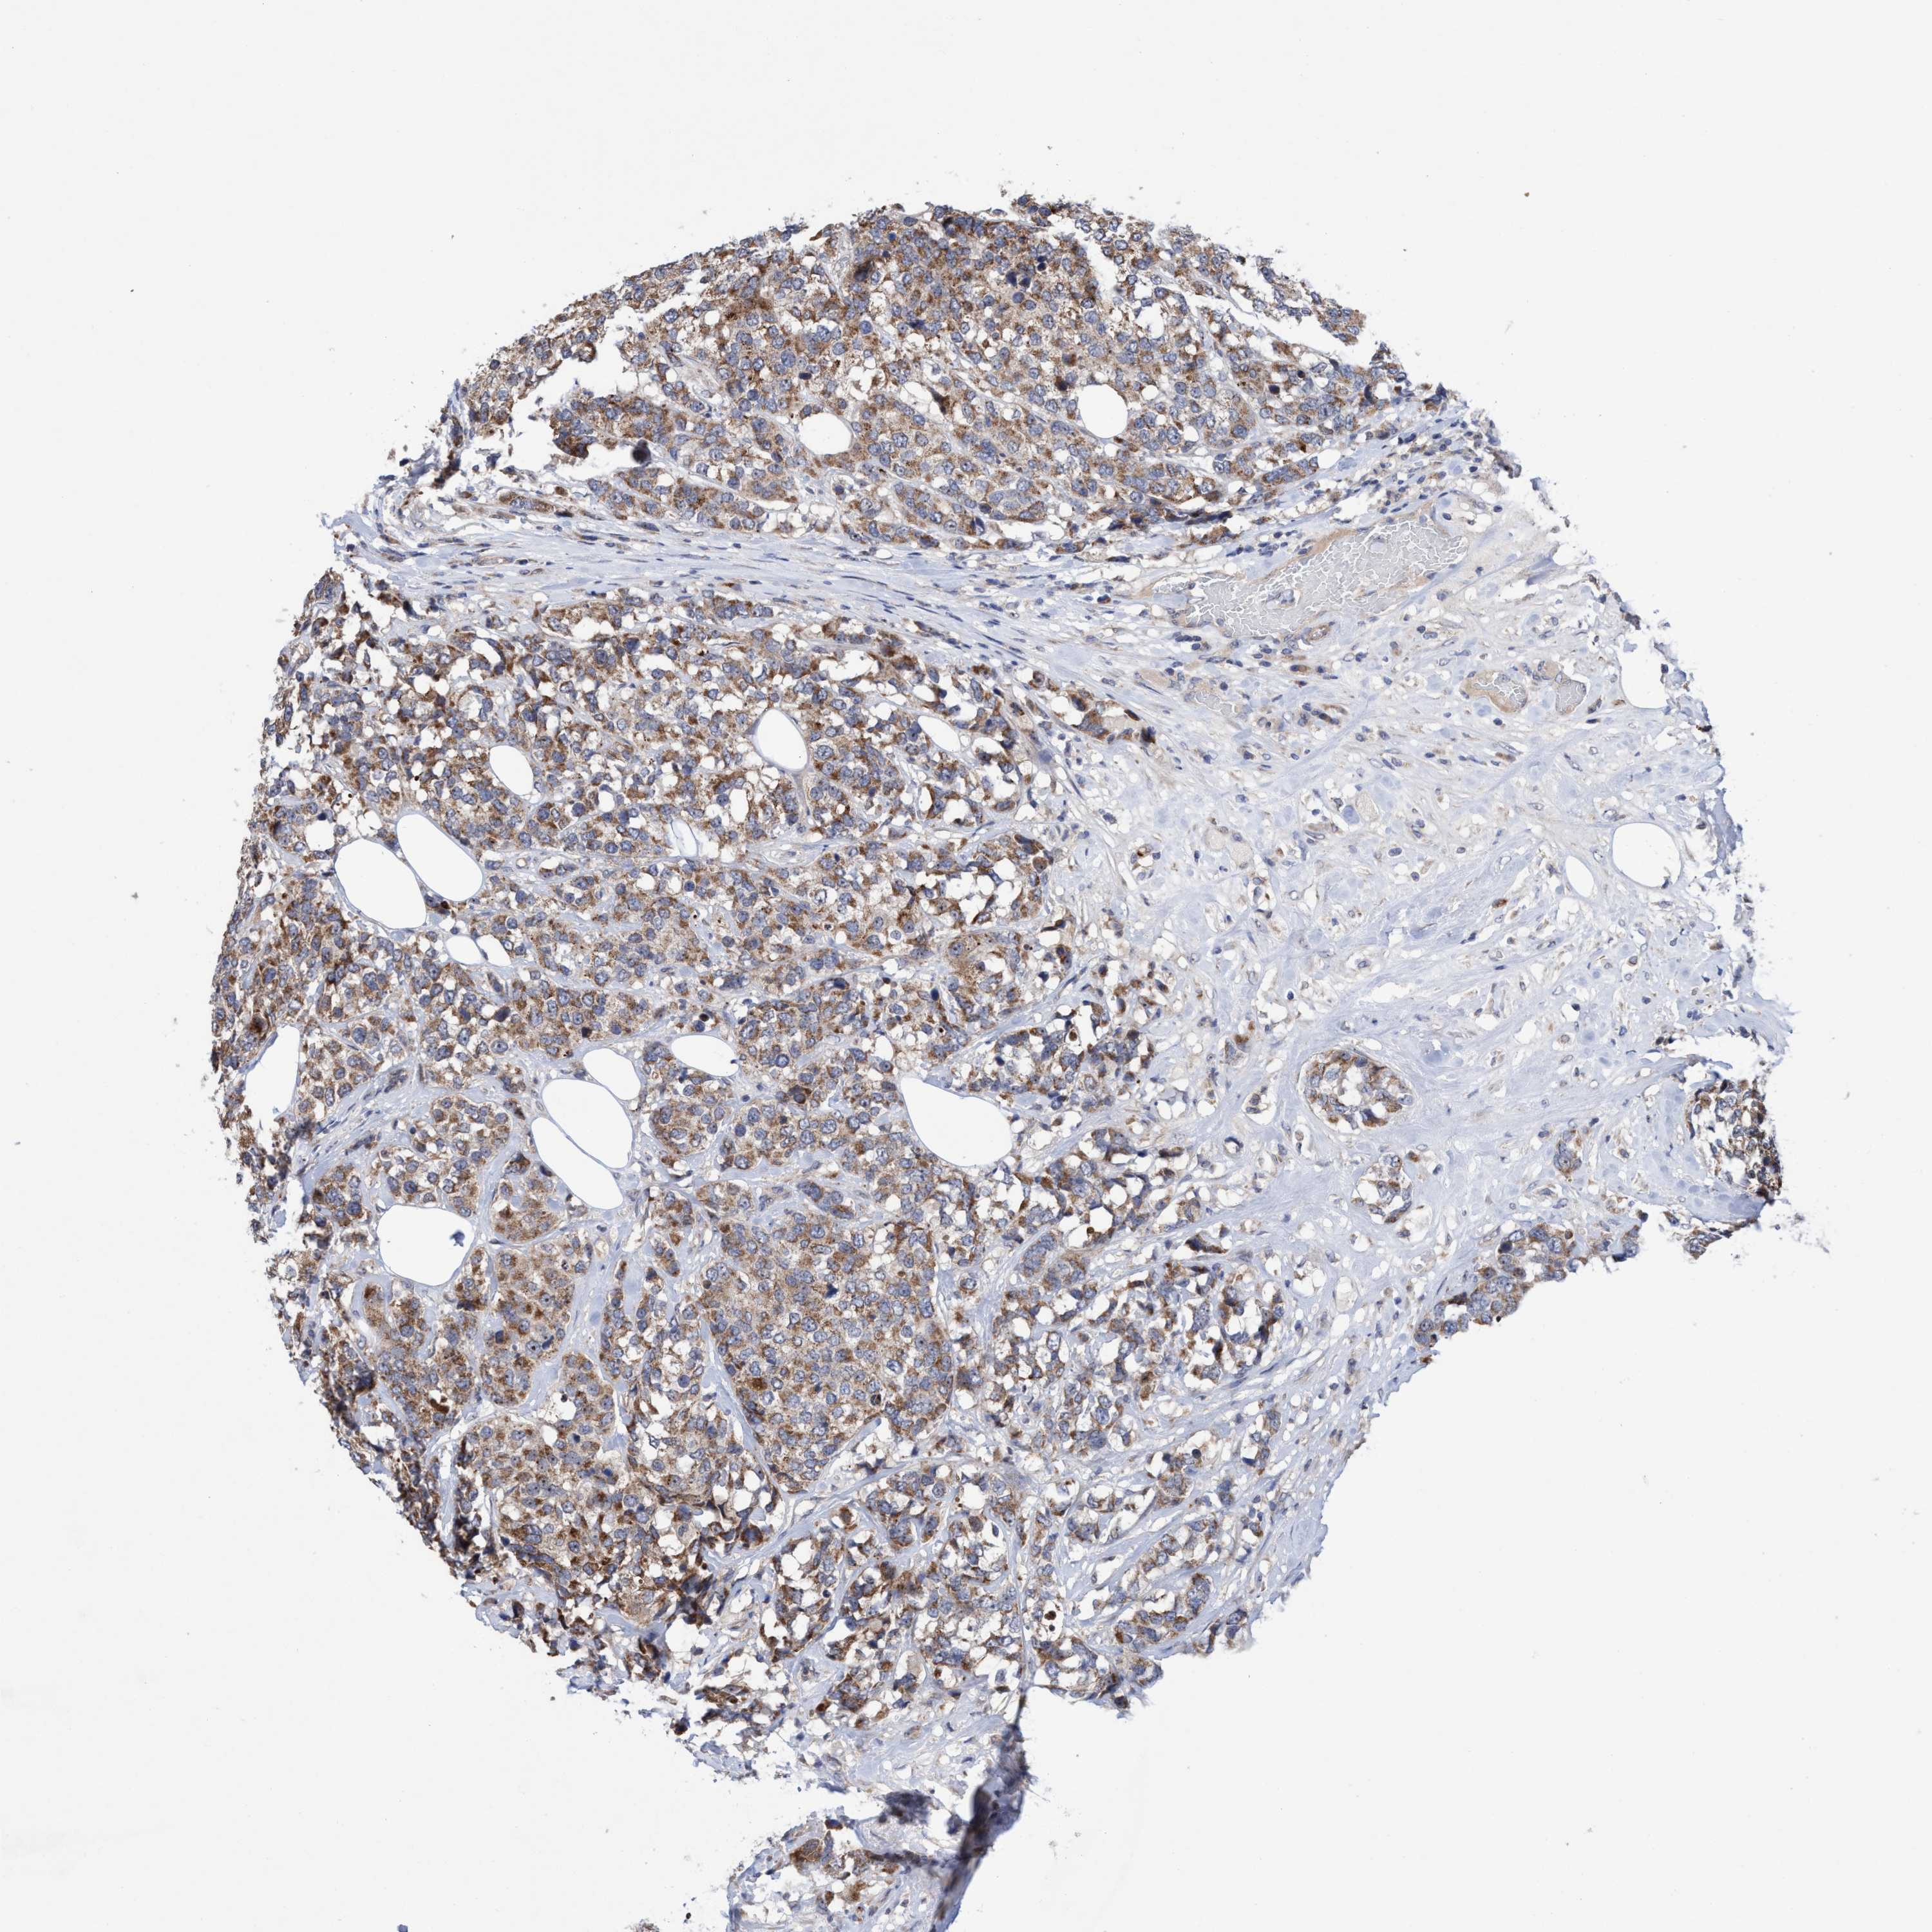

CANCER BREAST CANCER Show tissue menu

BRCA TCGA BRCA VALIDATION PROTEIN EXPRESSION